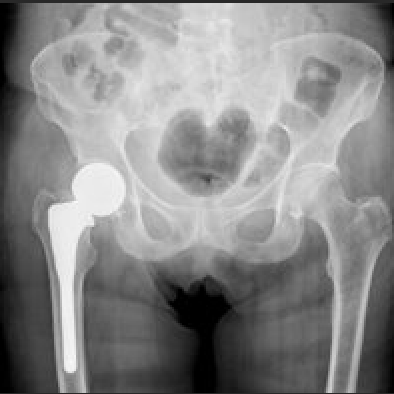

- It is most likely related to muscle soreness or arthritic changes in the hip joint.

Read my blog article if you want to learn more about hip fracture prevention. I have also written a blog post on hip protectors.